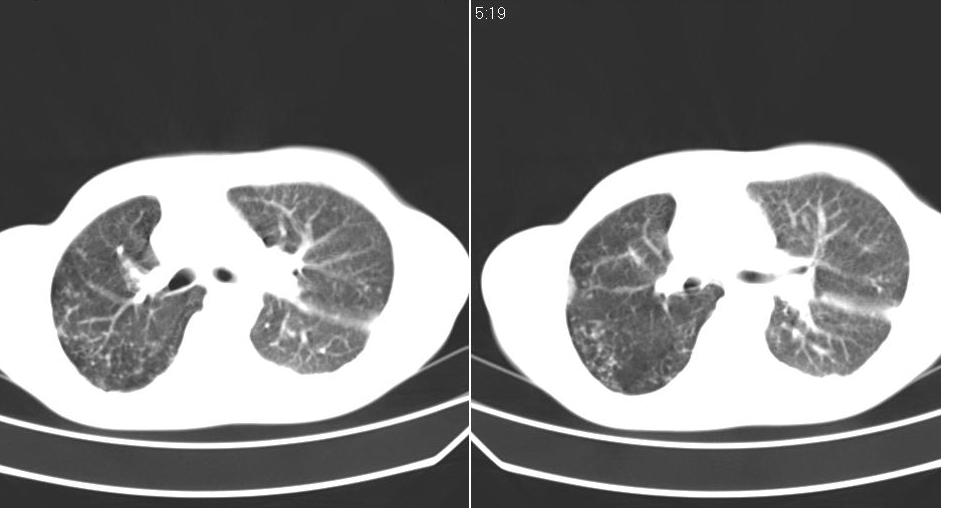

以下是引用苯小孩在2007-6-27 15:09:00的发言:[br]考虑:1、右肺继发性肺结核.2、双侧包裹性积液<胸腔及叶间>3、双侧局部胸膜增厚.[br]建议胸水化验检查.

以下是引用yanghaochen88在2007-6-27 15:08:00的发言:[br]双肺上野散在粟粒状影、包裹性积液、胸膜增厚粘连、叶间积液---tb,至于分型还得结合病史体征细究妥当些。